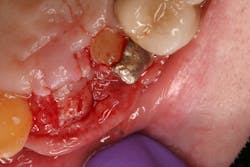

- Suture technique: lack of tension-free closure (figures 1 and 2), incision design doesn’t include keratinized tissue, failure to approximate tissue flaps (use of horizontal/vertical mattress helps)

- Surgical technique: failure to stabilize graft/membrane, lack of implant/cover-screw stability, insufficient amount of flap tissue in suture bite